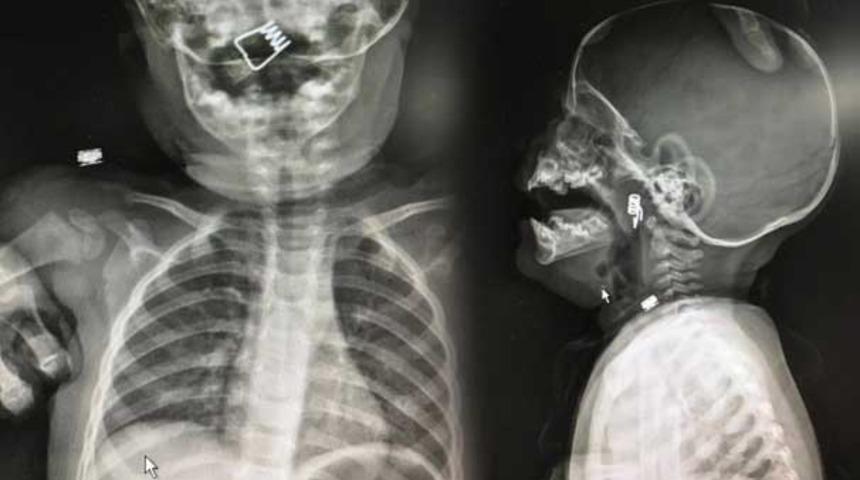

Nevşehir’de 1 yaşındaki Ö.Y.'nin boğazına mandal yayı kaçtı. Durumu fark eden aile hemenb soluğu hastanede aldı. Minik bebeğin nefes borusuna saplanan mandal yayı ameliyatla alındı.

Nevşehir Devlet Hastanesi Acil Polikliniği'ne getirilen bebeği, Acil Nöbetçi doktoru Mustafa Alpaslan muayene ederek gerekli tetkikleri yaptı. Çekilen röntgen filmlerinde mandal yayının lokalizasyonu ve durumu belirlendi. Daha sonra, KBB Uzmanı Op. Dr. Ahmet Cevatzade tarafından yapılan başarılı ameliyat sonucunda bebeğin genzine saplanan mandal yayı çıkartıldı.